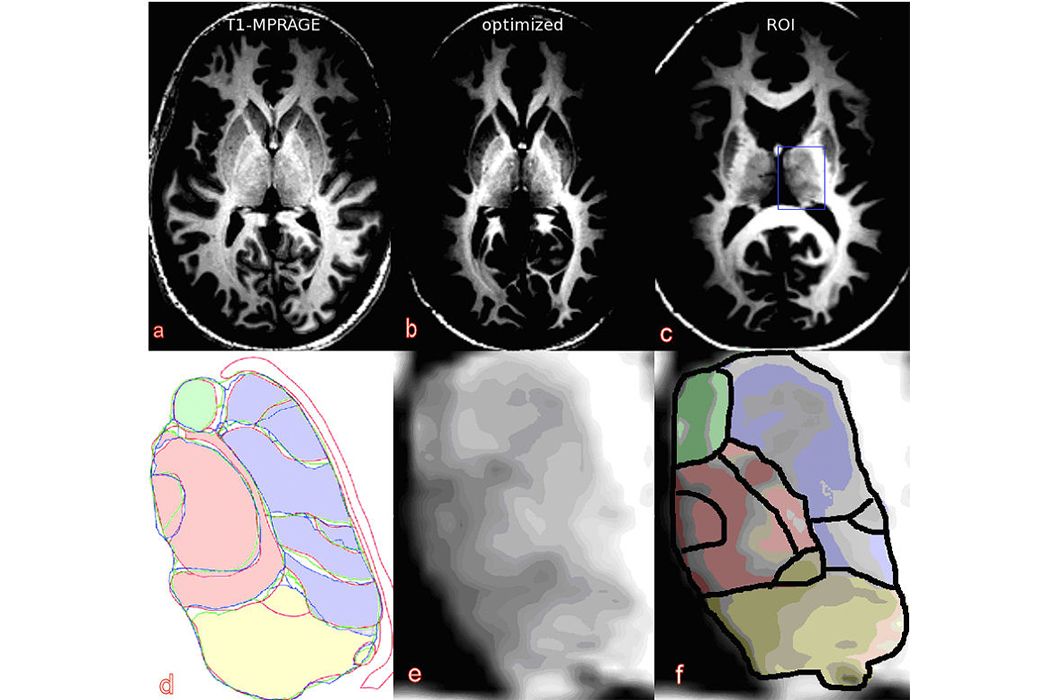

Die große Bedeutung der MR-Bildgebung für die radiologische Diagnostik beruht auf der sehr großen Variabilität des Kontrasts zwischen unterschiedlichen Geweben, der durch die Wahl der verwendeten Messsequenz bestimmt wird. Eine diagnostische Routineuntersuchung mit einem MR-Tomographen wird deshalb in den meisten Fällen mehrere Messsequenzen mit unterschiedlichen Signaleigenschaften enthalten. Dennoch können manche Strukturen im Körper nicht so differenziert abgebildet werden, wie es wünschenswert wäre. Eine dieser Strukturen ist der Thalamus.

Der Thalamus spielt eine wichtige Rolle als Zwischenstation von Afferenzen und Efferenzen der Großhirnrinde. Insbesondere bei Dystonien (Bewegungsstörungen) und dem Morbus Parkinson besteht die Möglichkeit, mittels Tiefenhirnstimulation in spezifischen Thalamuskernen eine Symptomverbesserung zu erreichen. Dabei werden auf diese Kerne elektrische Impulse über eine implantierte Elektrode übertragen. Um eine solche Elektrode richtig positionieren zu können, wird eine Bildgebungstechnik benötigt, die die Lage der Thalamuskerne zeigen kann.

Auf normalen anatomischen MR-Aufnahmen unterscheiden sich die Thalamuskerngebiete in ihrer Signalintensität jedoch zu gering, um sie identifizieren zu können. Das Ziel aktueller Forschungsarbeiten ist die Entwicklung von Messtechniken, die die Subeinheiten des Thalamus erkennbar werden lassen. Dabei werden besonders diffusionsgewichtete Sequenzen oder kontrastoptimierte 3D-Sequenzen untersucht.